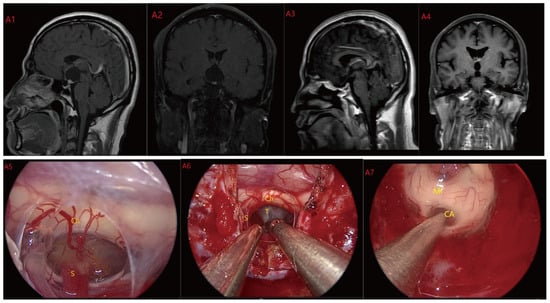

Figure 3.

Case 3 Type II: (B1,B2) The tumor was located on the suprasellar, growing upwards into the third ventricle, and it is impossible to judge whether the third ventricle floor was complete before operation. During the EEA surgery (B5–B8), the TCPCA and TLTA was used. The tumor was completely resected (B3,B4), and the floor of the third ventricle was seen to be incomplete. Optic chiasm (Ch), foramen of Monroe, massa intermedia (MI), cerebral aqueduct (CA), tumor (T).